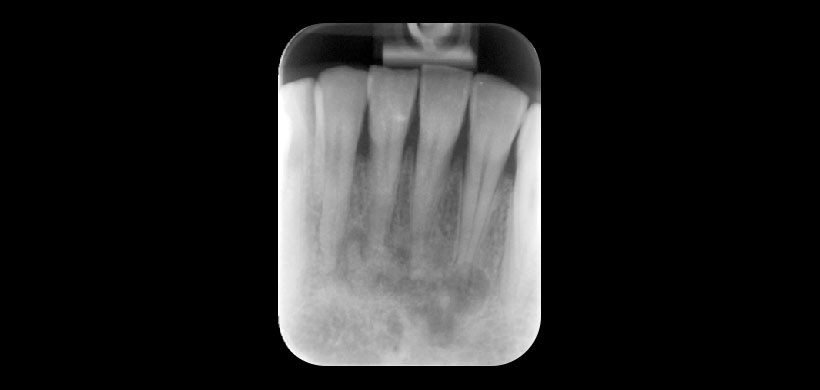

Fig 4. Radiografía periapical, muestra una imagen mixta (radiolúcida-radiopaca) de la lesión, se encuentra en los ápices de los incisivos inferiores. La lámina dura que rodean las zonas apicales de los dientes afectados se pierde.